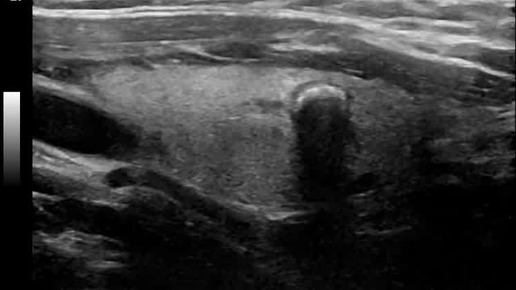

Видео к статье "Общие принципы ультразвукового анализа узлов щитовидной железы" Ссылка на статью https://dzen.ru/a/ZtlFLWAI93Gg_c_j